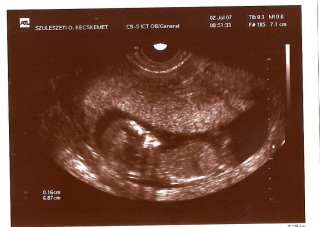

Igyekszem majd szkennelni képet Kismanóról! Már igazi baba-formája van, és nem nagyon komálta a vizsgálatot, úgy mozgott, hogy a dokinéni hosszú percekig üldözte egy villanásnyi szívhangért...

Apukája tátott szájjal és csillógó szemekkel figyelte, teljesen elérzékenyült, annyira édes volt! Szóval aki teheti: 12 hetes uhura apát is vinni!!!